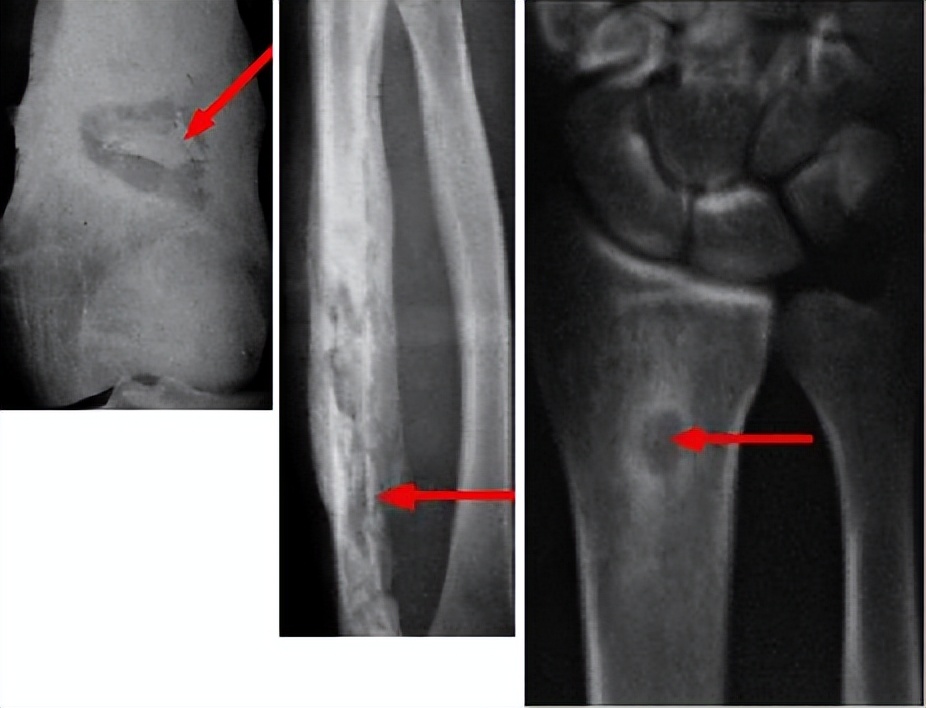

骨髓炎是骨科疾患当中一种较为严重的,因为细菌性感染而导致的一种疾病。此类患者大多数有开放性的软组织及骨的损伤。

骨髓炎的典型患病症状就是局部的红肿热痛。疾病高发者多为儿童和青少年,且男性患者比例要高于女性。

临床经验来看,最主要的原因就是肢体的开放性损伤、细菌的定值,再加上软组织损伤较重、骨质粉碎,骨组织失去正常血供,从而造成的肢体自身抗感染能力下降,容易受到细菌侵袭。